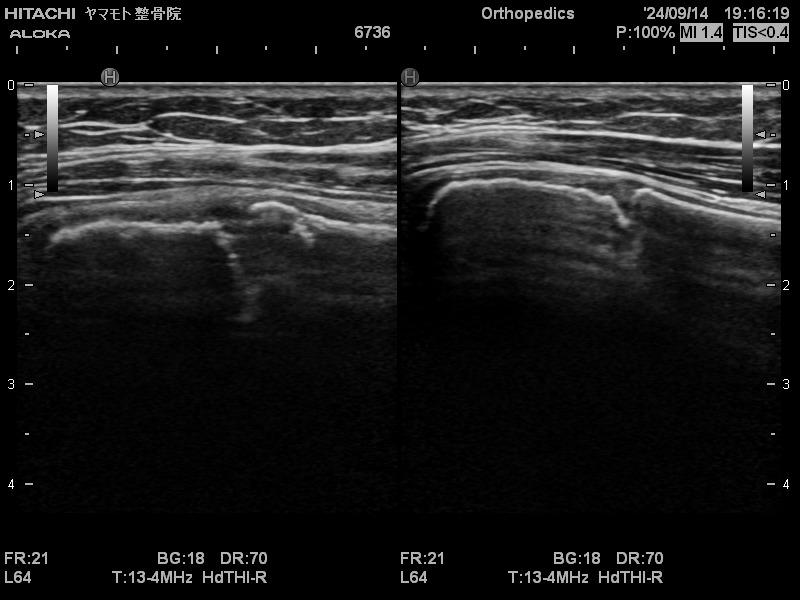

エコー検査

野球肩・野球肘のエコー

高精度エコー

最高峰の高精度エコーにより、野球肘・野球肩の細かな損傷も見逃さず、お身体の状態を把握します。

野球肩・野球肘のエコー画像

離断性骨軟骨炎

野球肘のガンとも言われる、最も難渋する疾患です。

絶対に見逃してはなりません。早期発見が最重要事項です。

エコー等の画像診断が無ければ早期発見は不可能と思われる障害です。